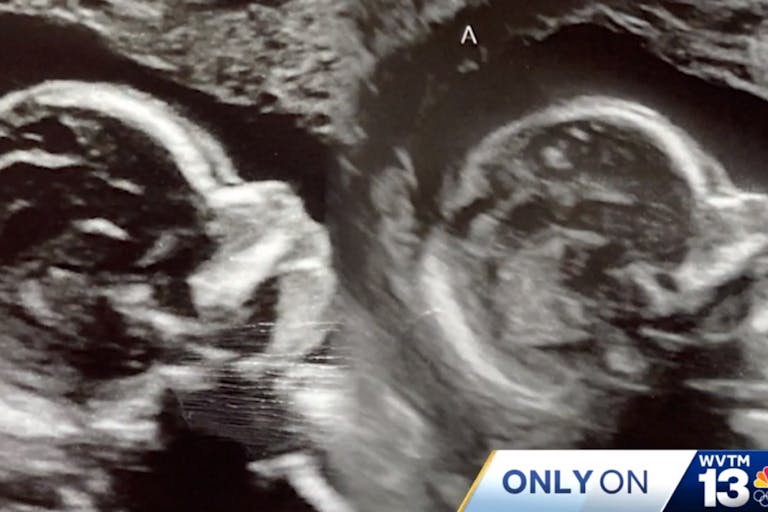

Kelsey Hatcher of Alabama knew she was born differently; specifically, she was born with two uteruses and two cervices. But in what doctors have called a “one in a million” chance, when Kelsey got pregnant, she found she was carrying two babies – one in each uterus.

And as statistics show, a double pregnancy in a uterus didelphys, as Kelsey’s condition is known, is vanishingly rare. Uterus didelphys forms in about 0.3% of women. “A double cervix or double uteruses way under 1% [sic], maybe three per 1,000 women might have that. And then the probability of you having a twin in each horn is really crazy,” said Dr. Richard Davis, a UAB maternal-fetal medicine specialist who is treating Kelsey, to WVTM13.

The nurse called in Kelsey’s obstetrician, Dr. Shweta Patel, who reviewed the scans several times and confirmed that in fact, Kelsey was pregnant with fraternal twin girls – one baby in each uterus. When asked how this could have occurred, Dr. Patel told GMA, “Most likely what happened is that she ovulated separately and had one egg come down each fallopian tube, meaning coming down on each side of the uterus, and then sperm traveled up on each separate uterus and fertilization occurred separately.”